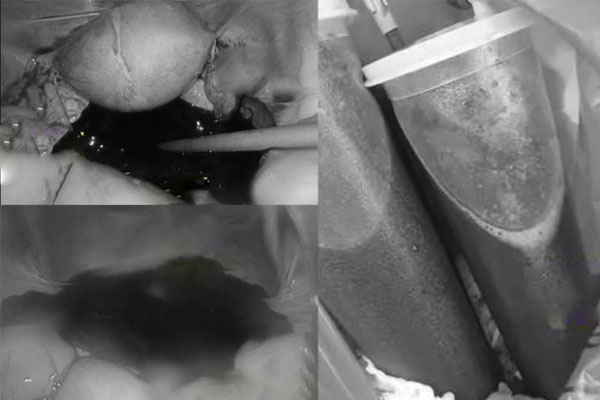

Tiến sĩ Lý Vệ Quân chính là người bạn học được nhắc tới, ông kể lại: “Ngay khi nghe mô tả các triệu chứng tôi đã nghi ngờ là vỡ hoàng thể. Khi nhập viện, bệnh nhân đau đớn và có hiện tượng chảy máu trong. Kiểm tra sâu hơn xác định đúng là bệnh nhân bị vỡ hoàng thể, dẫn tới xuất huyết tràn ổ bụng. Ngoại trừ khoang chậu, mọi thứ đều bị bao phủ bởi máu, ngay cả khu vực xung quanh gan cũng tràn ngập máu. Chúng tôi phải phẫu thuật khẩn cấp để cầm máu tránh bệnh nhân bị sốc mất máu nguy hiểm.

Đầu tiên, chúng tôi loại bỏ máu cả cản trở tầm nhìn, sau đó tìm điểm chảy máu buồng trứng, cắt bỏ nang hoàng thể để cầm máu, sau đó rửa sạch toàn bộ khoang bụng. Tổng lượng máu trong khoang bụng do vỡ hoàng thể là 1,5 lít. Ca phẫu thuật bằng hình thức nội soi để giảm xâm lấn. May mắn là tới bệnh viện kịp thời, mọi thứ đều được xử lý tốt nên bệnh nhân hồi phục nhanh, buồng trứng được bảo tồn tốt”.